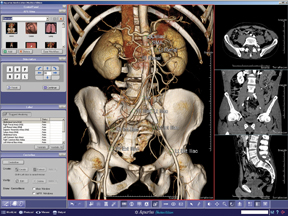

Aquarius iNtuition by TeraRecon offers a range of options to deliver an advanced, procedural workstation configuration for the 3D technologist, a powerful reading / browsing station for the diagnosing physician and a fast, simple 3D review tool.

As the latest generations of magnetic resonance imaging systems (MRI), computer tomography systems (CT) and 3D ultrasound render volumetric images with high resolution and detailed anatomical information, enabling clinicians to better depict anatomies. Medical anomalies are greatly improved as the imaging industry leverages the potential that can be reached using new mathematics and algorithms for image enhancement, projections and rendering. In addition, the use of high-speed computation technology in multiple core computers and graphics processors makes advanced medical images instantly available.

Short and long-term image storage remains a challenge for hospital administrators as well as stand-alone imaging centers, as storing and retrieving data must be transparent to physicians. Today’s physicians demand instant and online access to images from the CT, MR or ultrasound system. Images must be available with a few clicks of the mouse, placing high requirements on accessibility. The image size and resolution have increased considerably, and in volumetric imaging the amount of data has multiplied, creating a bottleneck. This increase of data requires novel compression techniques and ultrafast storage media. All parts of the image chain, from the detector to the PACS and the workstation, can be optimized for speed and flexibility.

Developers continue to create faster and more efficient mathematical algorithms and advance computer hardware technology. These advancements enable volumetric image enhancement at astonishing speeds, with 3D images available instantaneously.

New diagnostic tools based on mathematical algorithms requiring computational power are the way of the future. The result will be fast data accessibility, which will give physicians new ways to review and explore multidimensional data, thereby improving the diagnostic outcome.